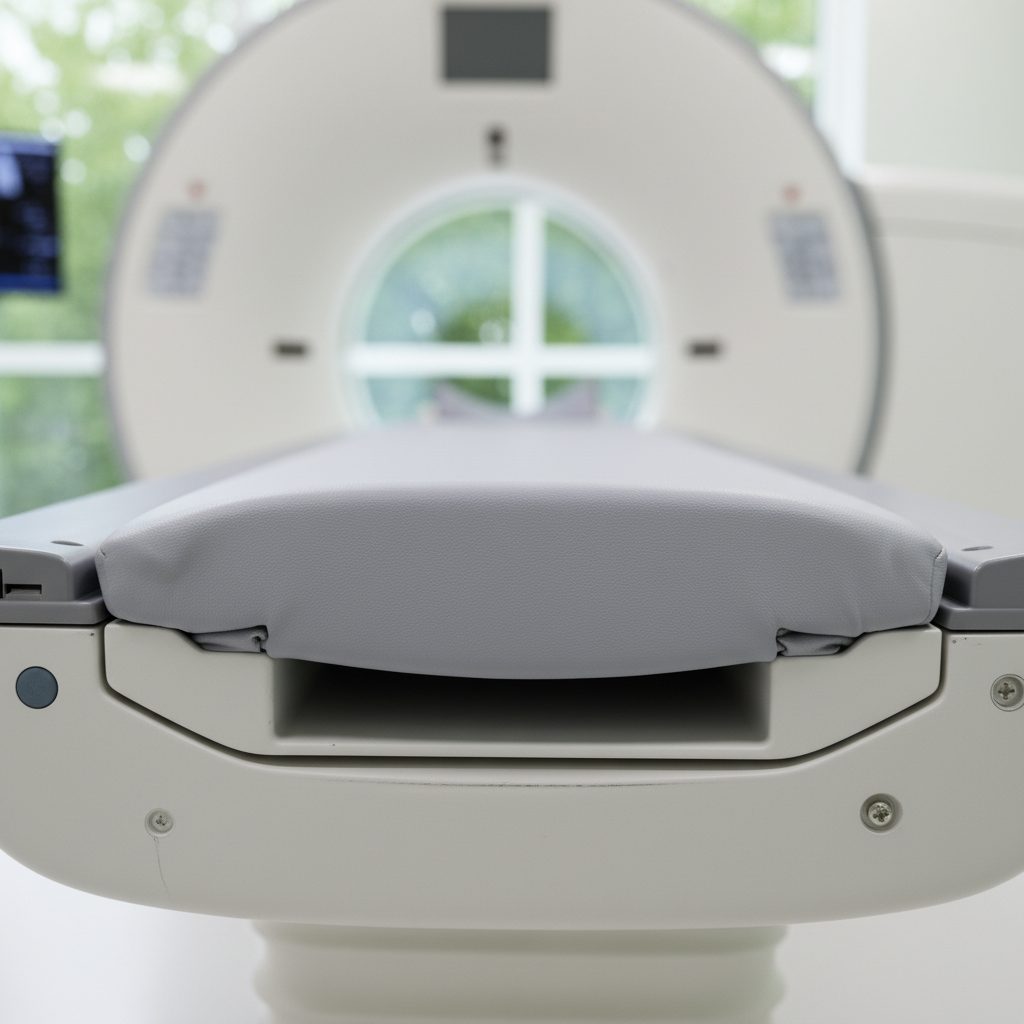

У меня установлено современное оборудование, включая:

— Компьютерный томограф Toshiba 64, с выполненным апгрейдом до 128 срезов,

— Производство Япония — гарантия качества и долговечности,

— Новая рентгеновская трубка — дополнительная надежность для вашего бизнеса.